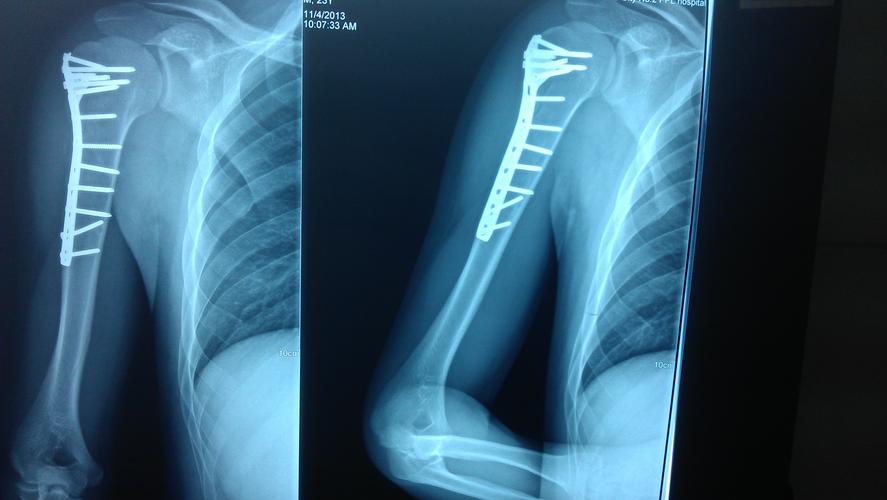

左肱骨近端骨折图片

左肱骨近端骨折图片,股骨近端骨折

肱骨近端骨折

肱骨骨折图片

肱骨近端骨折图片

肱骨近端骨折内固定

肱骨近端骨折术后

肱骨近端骨折钢板

肱骨近端骨折手术